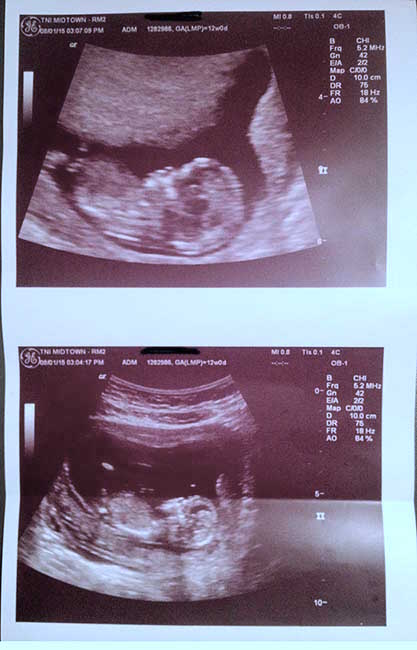

First time parent here. We just came back from our 12weeks 4days ultrasound and the tech did not even try to guess this one. Anyone here care to try a guess.

Is it a girl? :DD: or a boy? :DS:

Can't see a nub in the second one. The first and last is head to chest and not sure about skull theory, sorry x

I think I see a classic boy nub in the 2nd pic but the image is small.

I'm with MM.. See classic boy nub in middle pics

Boy guess off second pic too :)

Boy off of second pic for sure